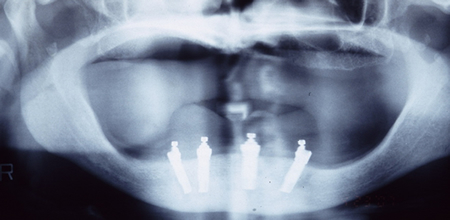

インプラント治療時には、CT検査を行い顎骨の状態を詳しく調べます。通常はまず、局所麻酔下に顎にドリルで穴を開け、インプラント体の埋め込み手術を行います(一次手術)。その後、インプラントと骨が結合するまで、約3~6か月間の治癒期間をおきます。骨と結合した時点で、歯肉を少し切開し(二次手術)、人工歯を取り付けます。骨の状態がよい場合にかぎり、1日でインプラント埋入手術から人工歯の取り付けまでの治療も行っています。

| インプラント埋入手術 | 人口歯の取り付け | ||

ドリルで顎に穴を開ける |

インプラント体を埋め込み |